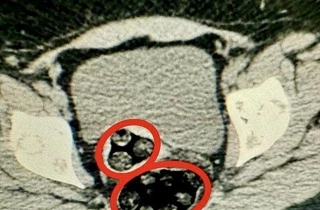

Burada çekilen röntgende, kadının bağırsağında 94 parça halinde 550,93 gram sentetik uyuşturucu tespit edildi.